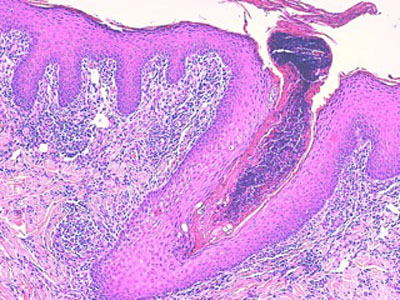

Histologie : L ‘épiderme et les infundibula folliculaires sont hyperplasiques, sièges d’une acanthose régulière d’intensité modérée, associée à une hyperpigmentation et à une hyperkératose tantôt orthokératosique, tantôt focalement parakératosique d’intensité modérée. La couche cornée est ainsi épaissie, croûteuse, stratifiée. L’épiderme et les structures infundibulaires, sont le siège d’une régulière exocytose de petits lymphocytes et plus rarement de neutrophiles. Dans le derme, les sacs folliculaires sont rarement rompus et les glandes sudorales font l’objet de remaniements inflammatoires chroniques, plasmocytaires. Au sein de la kératine libre péri-pilaire et au sein de la couche cornée de l’épiderme, on observe de rares hyphes mycéliennes PAS positives.

dermatophytose-atypiqueh1-jpegEFH1